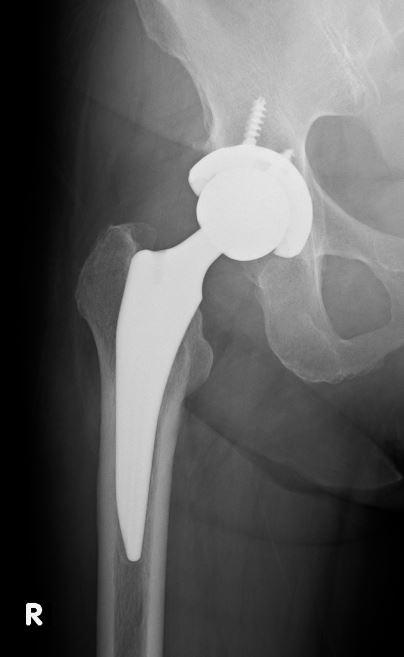

人工股関節置換術を受けた患者さんは、骨密度の変化が局所的に発生することがあります。そのため、人工股関節の周囲をいくつかの領域(ゾーン)に分け、それぞれのゾーンごとに骨密度を測定し評価することで、どの部位で骨密度が低下しているかを明確にすることができます。骨密度が特定の部位で顕著に低下している場合、それに対して予防や治療が行いやすくなります。

人工股関節のX線画像 |